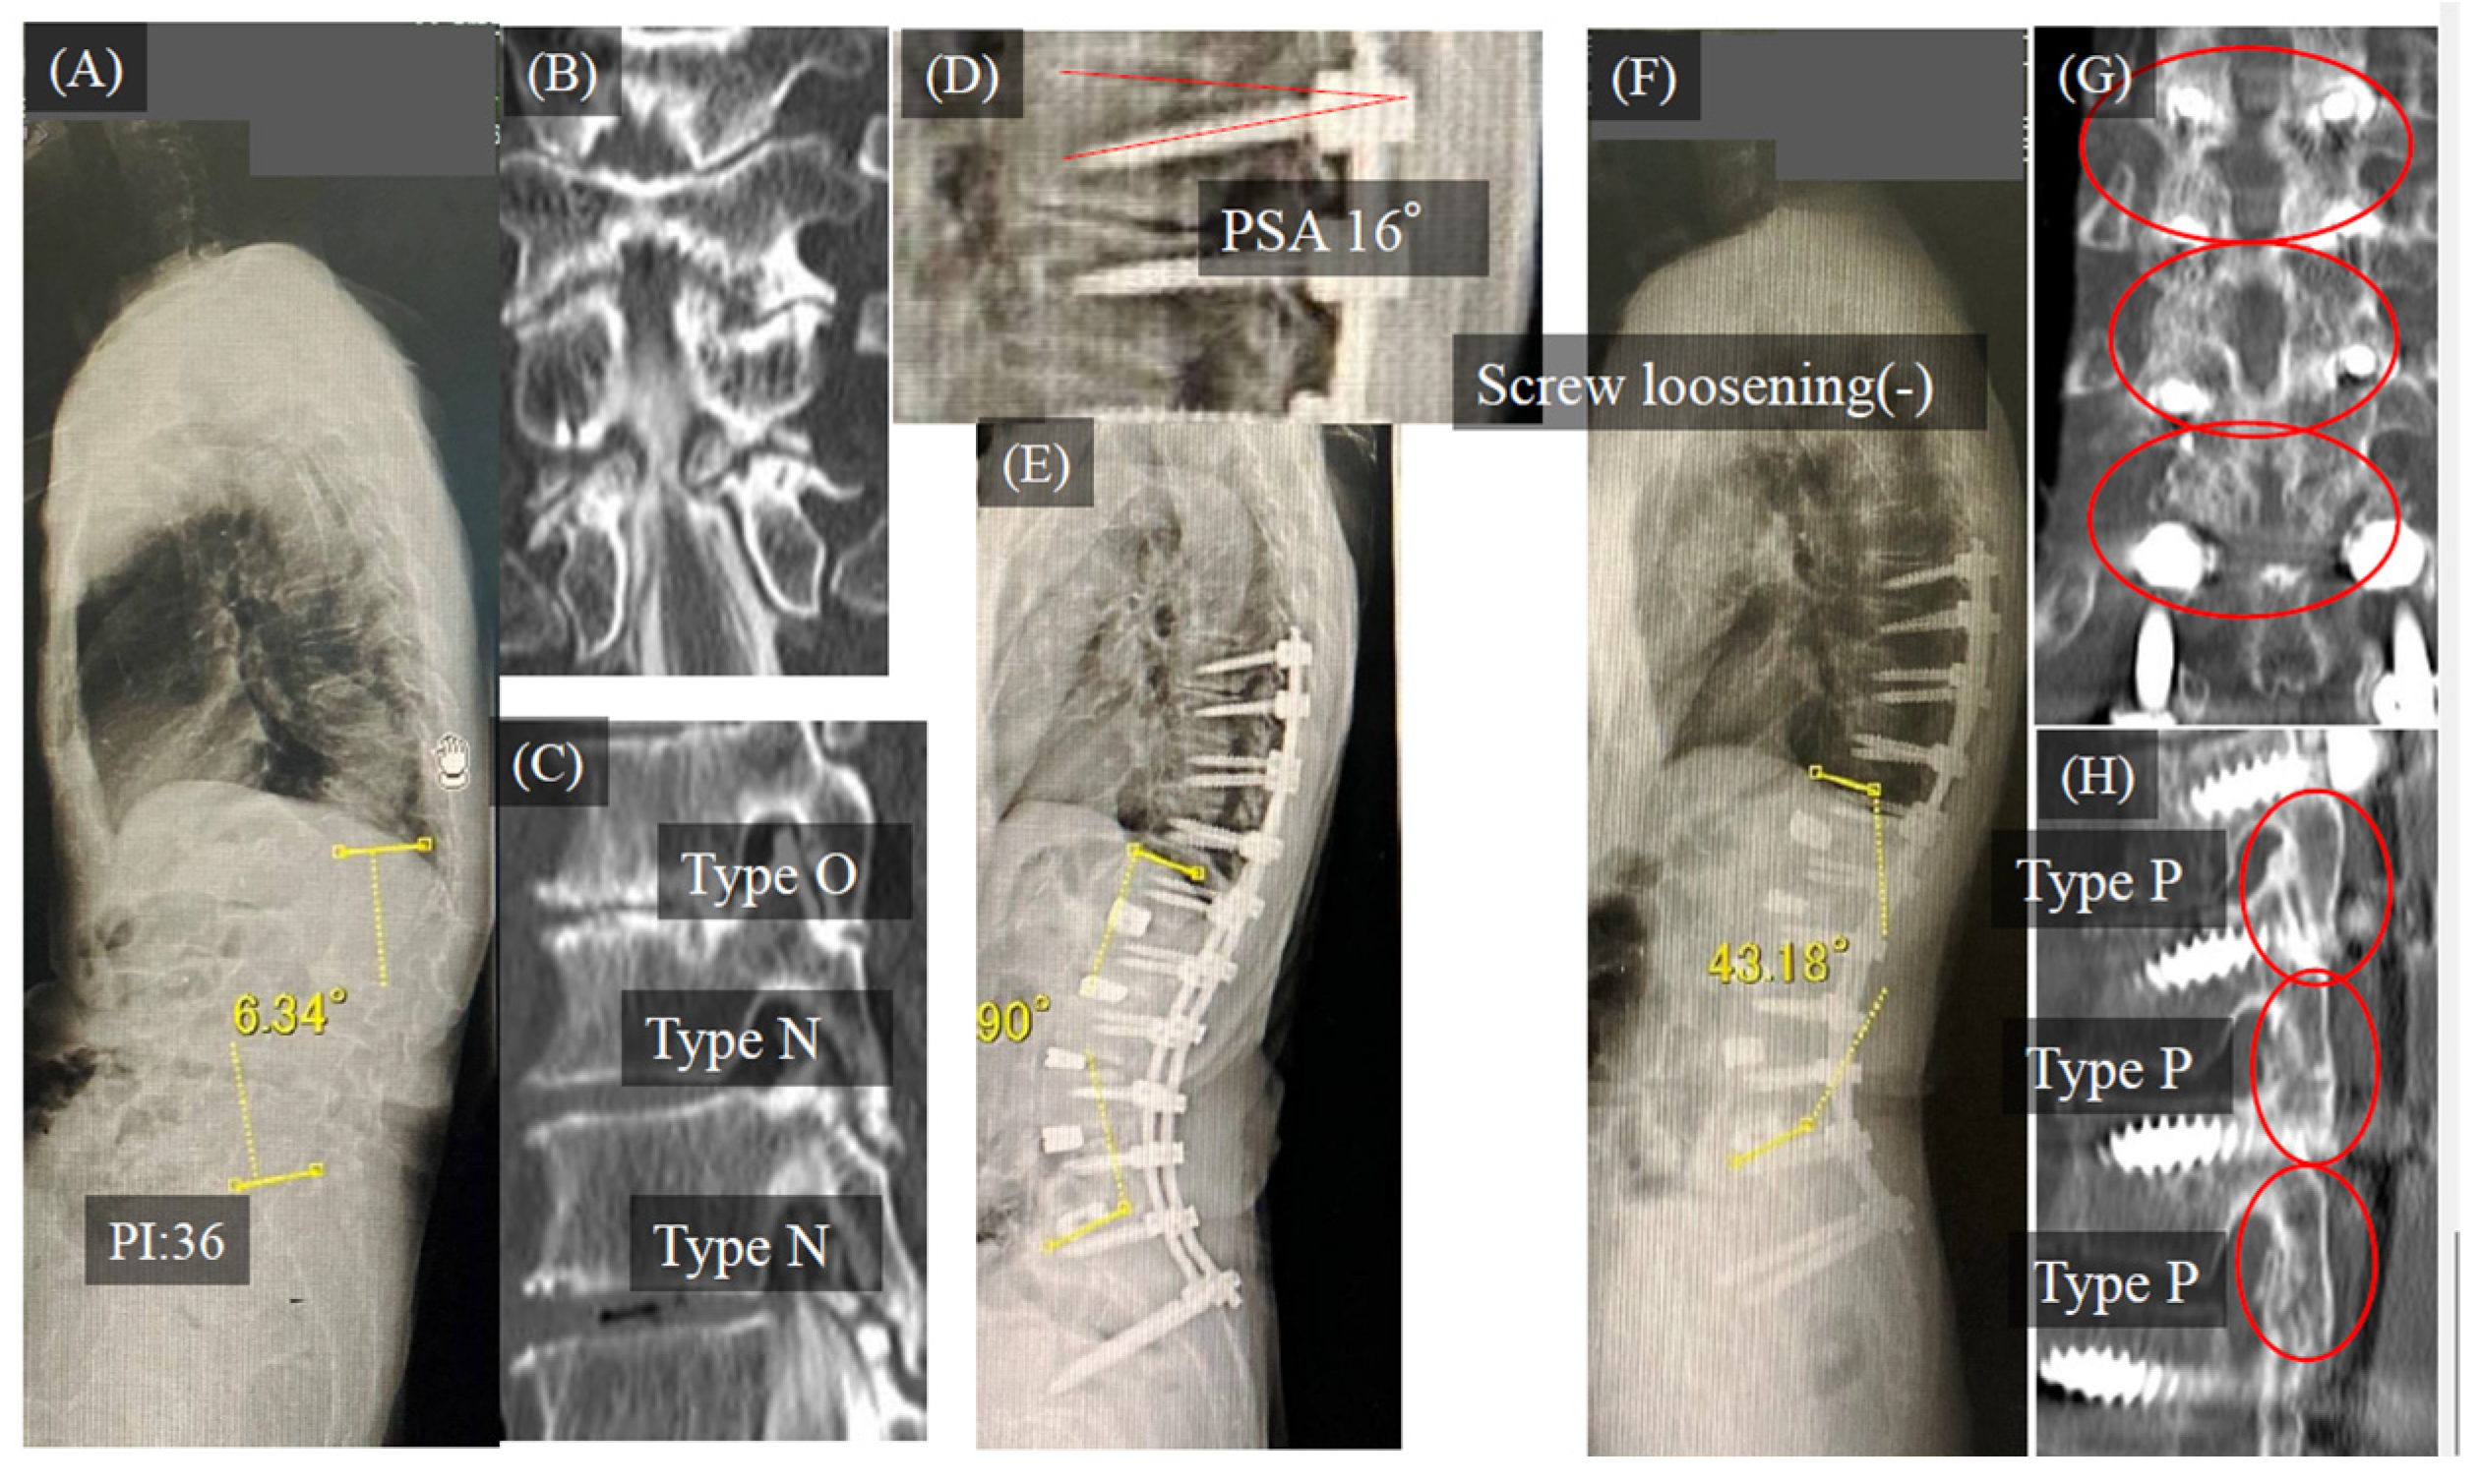

3.1. Case Study

Case Study 1